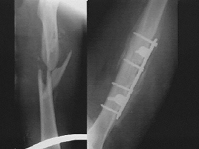

Рентгенограмма правого бедра в передней и боковой проекции от 04.10.2011.

На рентгенограмме правой бедренной кости в прямой проекции от 01.10.2011 (по месту жительства) определяется косой закрытый диафизарный перелом бедренной кости в верхней трети со смещением отломков. На контрольных снимках правой бедренной кости от 04.10.2011, в палате, после установки системы скелетного вытяжения с грузом по оси - 6 кг. Отломки расположены со смещением.

Рентгенограмма правого бедра в передней и боковой проекции от 19.10.2011

На рентгенограмме правого коленного сустава в двух проекциях дистальное блокирование перелома правой бедренной кости при интрамедуллярном металлоостеосинтезе осуществлена 2 винтами. Снимки выполнены с ротацией коленного сустава ЭЭД= 0,003. На ренгенограммах черепа и скуловых костей определяется оскольчатый перелом правой скуловой кости. Фиксация осуществлена 1 спицей Киршнера. Смещение отломков сохраняется. Стояние их удовлетворительное. ЭЭД=0,091.